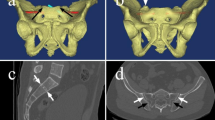

After identification of the patient’s CT scans, two musculoskeletal radiologists independently identified features of dysmorphic sacra. For the purposes of this study, these features included: (1) an upper segment that is not recessed in the pelvis, (2) the presence of mammillary bodies, (3) an acute alar slope, (4) a residual disc between the first and second sacral segments, and (5) noncircular upper sacral neural foramina (Fig. 1). These features were chosen based on prior study on sacral morphology with regard to sacral dysmorphism [15,16,17,18]. Sacra with four or five features were classified as dysmorphic.

A Hounsfield unit value for each sacral segment was then calculated adapting the methodology from Salazar et al. [20]. For each sacral segment, four circular regions of interest (ROIs) were strategically placed utilizing the axial CT sections (Fig. 2). The ROIs were placed into the anterior, posterior, right lateral, and left lateral aspects of each sacral body utilizing the axial CT imaging via the picture archiving and communication system (PACS) software. These were positioned to minimize overlap among the individual ROIs. Once placed, a HU value was obtained for each ROI. The four values were then averaged to arrive at a single HU value for each sacral segment.